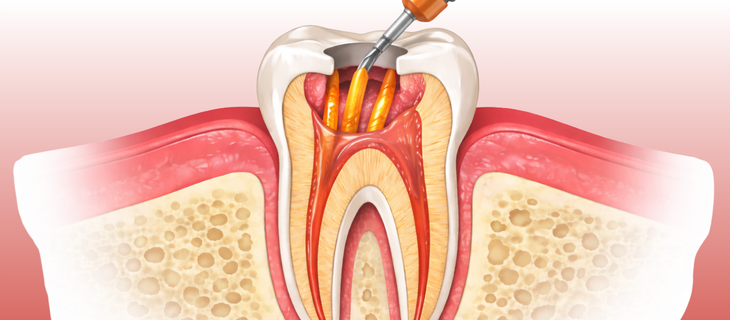

Non-Surgical Root Canal

Non-Surgical Root Canal Treatment

This is the most common form of root canal treatment. The infection is treated by cleaning the canals from inside the tooth, without any cutting on the gums. It is usually done for teeth affected by deep cavities, infection, or damaged pulp. Most root canal problems can be treated without surgery, especially when the issue is identified on time.

Clean Those Root Canals

Root Canal

All infected tissue is carefully removed and the root canals are thoroughly cleaned and disinfected.